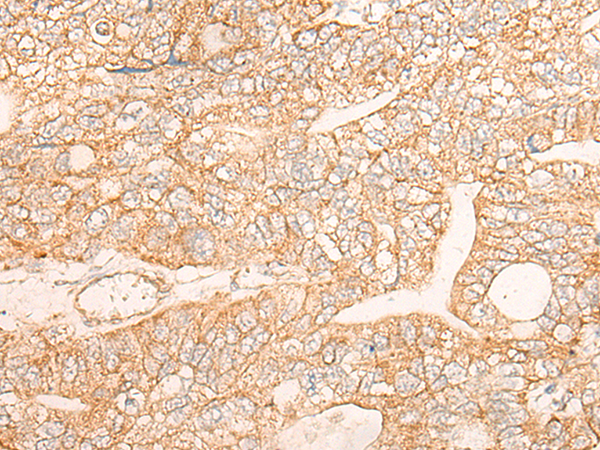

IHC positive control: |

Human liver cancer and Human gastric cancer |

IHC Recommend dilution: |

30-150 |